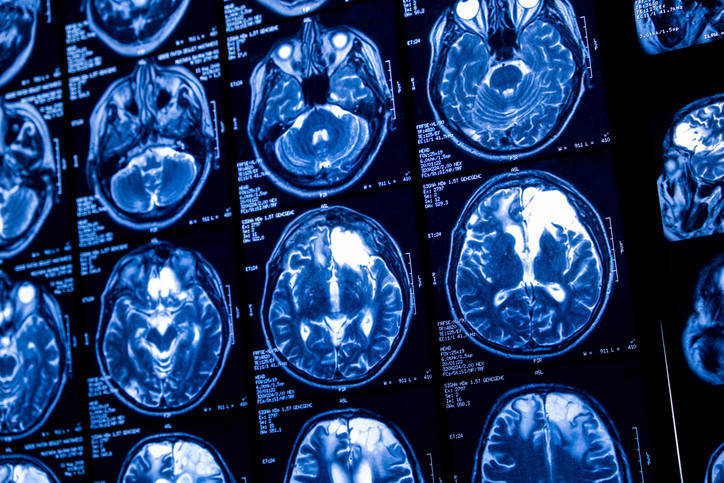

Yaklaşık 3 hafta sonra, Stuart Hill 7 saat süren büyük bir ameliyata alındı. Cerrahlar tümörü tamamen çıkarmayı başardı. Kitlenin beynin içine yayılmadığı, ancak beyin zarıyla kafatasına tutunduğu ifade edildi.

Operasyon sırasında kafatasının bir bölümünün çıkarılması gerekti ve bu bölüm kemik çimentosu kullanılarak yeniden yapıldı. Ameliyat teknik olarak başarılı geçti ancak sonrasında yeni bir sorun ortaya çıktı.